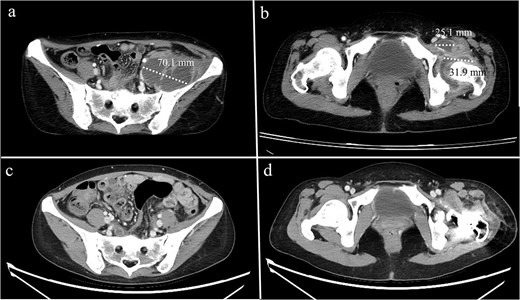

A 68-year-old male with a history of pelvic ring injury (fixation with two iliac screws 10 years prior) and degenerative lumbar spondylosis (spinal instrumentation 1 year prior) presented to the emergency department with fever and buttock pain. Magnetic resonance imaging revealed bilateral lobulated abscesses in the iliopsoas muscle (Fig. 5a–c). However, the abscess in the right psoas muscle extended caudally to the ischial tubercle and adductor muscles of the right thigh. Due to persistent fever with intractable pain in the right lower abdomen and right thigh, surgical debridement of the right psoas abscess was planned. The left psoas muscle was drained using a percutaneous CT-guided procedure because it was a solitary lesion.

MRI of a 68-year-old male with (a) bilateral psoas abscesses (right: 43.6 mm, left: 84.9 mm). The right abscess extended caudally to (b) the quadrilateral plate of the acetabulum and (c) the medial thigh and ischial tuberosity region. (d) Partial resolution of the right abscess with persistence of the left abscess (*). (e) Complete resolution of the right caudal extension after debridement.

The surgical procedure using the pararectus approach was similar to that used in Case 1. Surgical debridement was extended to the medial thigh and posterior buttocks (Fig. 6). Approximately 300 ml of pus was drained during surgical debridement. The bacterial culture yielded Streptococcus pyogenes. Serum CRP levels decreased progressively after surgery (Fig. 3). A repeat CT scan revealed a small residual abscess over the right iliac fossa with complete resolution of the infection of the left thigh and posterior buttocks (Fig. 5c and d). However, the resolution process was slow in the left psoas abscess treated with percutaneous drainage.